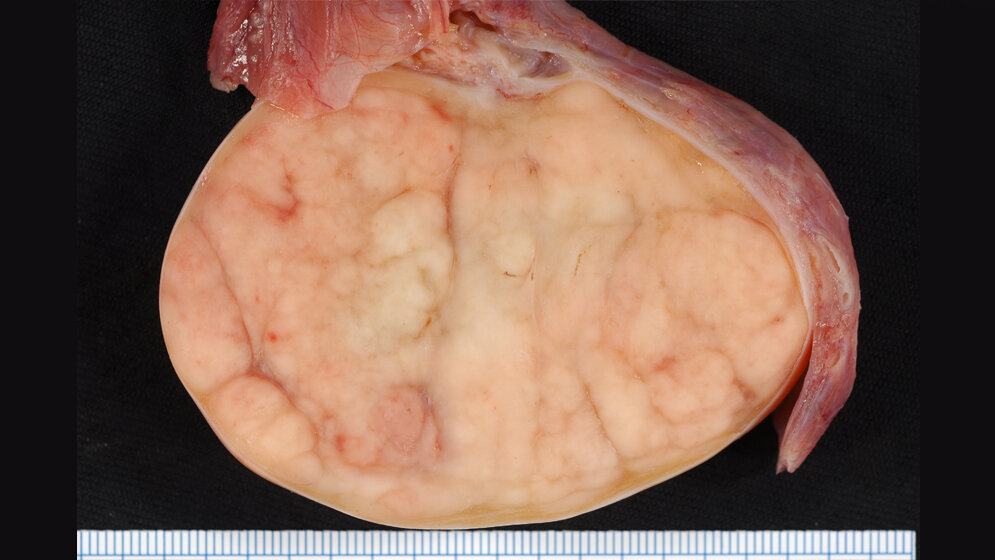

Bereits 2012 konnte das Forschungsteam in der Vorstudie über den neuen Tumormarker bei Hodentumoren berichten. Das Ergebnis mehrjähriger Folgestudien ist nun ein Verfahren zur sicheren Bestimmung der Tumormarker. Der sogenannte Signalstoff M371 wird von den Hodenkrebszellen gebildet und in die Blutbahn ausgeschüttet. Die Urologen um Prof. Dieckmann und seine Partner von der biologischen Fakultät der Universität Bremen konnten zeigen, dass bereits sehr kleine Tumore von weniger als 1 cm Durchmesser den Signalstoff abgeben. „Dies ist ein großer Fortschritt“, so Dieckmann, „denn der M371-Test ist bei mehr als 90 % aller Hodentumoren anwendbar. Die bisherigen Markerstoffe sind nur bei etwa 50 % aller Patienten ausgeprägt. Der neue Test hilft bei der Früherkennung, bei der Ausbreitungsdiagnostik, bei der Feststellung des Therapieerfolges und vor allem bei der Früherkennung von Rückfällen. Wir denken auch, dass bei der Nachsorge viele der schädlichen, belastenden und teuren Röntgenuntersuchungen mit dem Test nicht mehr nötig sind.“